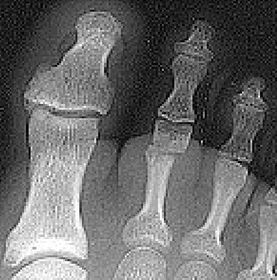

| Describe the alignment of metatarsal 2 | There is no angulation nor displacement of the distal segment relative to the proximal segment. |

| Describe the alignment of metatarsal 3 | The distal segment is displaced laterally (50% apposition) and angulated medially. |

| Describe the alignment of metatarsal 4 | The distal segment is displaced laterally (75% apposition) but there is no apparent angulation. |

| Describe the tubulation of the metatarsals | Metatarsals are overtubulated - decreased girth. |